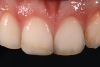

In anterior teeth, the risk of postoperative sensitivity is lower, and the enamel quantity is generally higher. For these reasons, clinicians should consider following an etch-and-rinse approach to obtain higher bond values. This second case report describes a Class IV restoration treated with a universal adhesive applied in etch-and-rinse mode. The patient presented to the office complaining about the esthetic appearance of tooth No. 8, which had a restoration that was performed 5 years earlier after a traumatic accident (Figure 6). The tooth still demonstrated vitality; therefore, the placement of another direct restoration was proposed and accepted by the patient. First, the previous restoration was removed, and the margin was prepared with a chamfer design (Figure 7). After adhesive procedures were performed with a universal adhesive applied in etch-and-rinse mode (Figure 8), the tooth was restored with composite materials in appropriate opaque and translucent shades with the help of a silicone index and sectional matrices (Figure 9 and Figure 10).

(6.) Pretreatment photograph of an existing composite restoration on tooth No. 8 that was placed 5 years prior to presentation following a traumatic injury. The patient was not satisfied with the esthetic appearance of the restoration.

Figure 6

(10.) Follow-up photograph of the final restoration taken 6 months postoperatively.

Figure 10